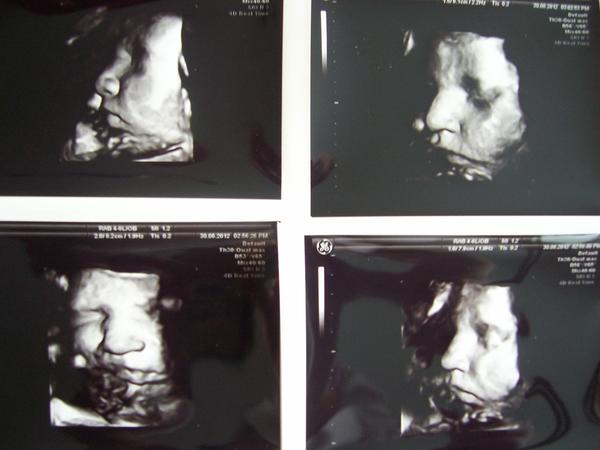

@darazv Ahoj,já byla také nachlazená hned po IVF a bála jsem ,se že ten kašel mi to zkazí a přesto to vyšlo.. 😉 Neztrácej proto naději, ale šetři se.. 🙂 Je to hnus být nemocná v těch vedrech,to ti věřím..a co teprve být v 8.měsíci..:-O Ale to už vydržím,že jo 😉 😎 Tak včera jsme už pár 3D fotek vytvořili,ručička na oku zmizela,ale byl tam ve spodní části pupečník,takže nějaké nerovnosti zůstaly..ale mám aspoň něco a už ji dál nebudu trápit 😅 Přikládám fotečky ,co jsem dostala 🙂 přeju Vám všem brzy podobné snímečky vlastních prcků.. 😵 😵 😵